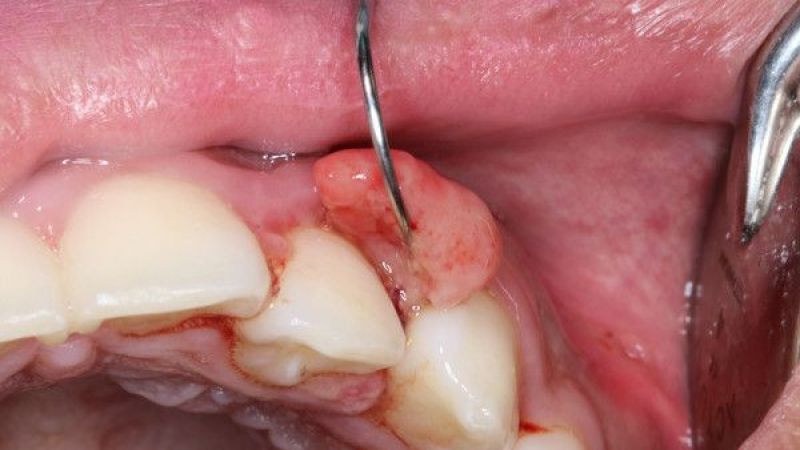

Ağız kanserine karşı uyarılarda bulunan uzmanlar, bu kanser türünün bazı belirtiler ile kendisini hissettirdiğini ifade etti. Söz konusu belirtiler ise genel çerçevede şu şekilde sıralandı:

- Boğuk ses

- Peltek konuşma

- Dili düzgün çıkaramama

- Uyuşma

- Çene sertliği

- Kulak ağrısı

- Dudak ve dilde uyuşma

- Dişlerin sallanması

- Devamlı kulak çınlaması